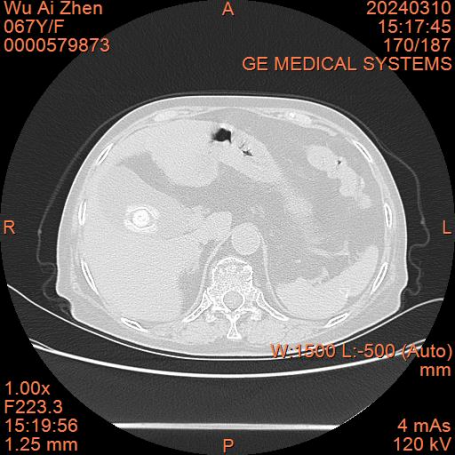

67歲的吳阿姨是一位紅斑狼瘡患者,長期服用激素類及免疫抑制類藥物。此次因突發上腹疼痛2天入院,入院后經醫師仔細詢問病史,分析病情,完善檢查后確診為膽囊結石并急性膽囊炎,請肝膽胰外科劉芳主任會診。劉芳主任會診后,結合患者實際情況,細致分析:1.患者在長期口服激素及免疫抑制藥物的情況下,仍有明確的膽囊結石并急性膽囊炎癥狀,說明實際病情比表現出來的要嚴重。2.患者除紅斑狼瘡外還合并有糖尿病,眾所周知糖尿病患者感染癥狀不易控制,容易繼發膿腫壞疽。3.患者年紀較大,基礎疾病復雜,膽囊結石已是第二次發作,隨著年齡的增長及基礎疾病的發展,手術風險及難度呈幾何倍數增長。綜合分析患者病情決定為患者行“腹腔鏡膽囊切除術”。

經過術前與患者及家屬溝通,完善了各項術前檢查,并請相關科室會診,成功為患者實施腹腔鏡膽囊切除術。在精心的治療和護理團隊的悉心護理下,患者恢復良好,于近日已康復出院。